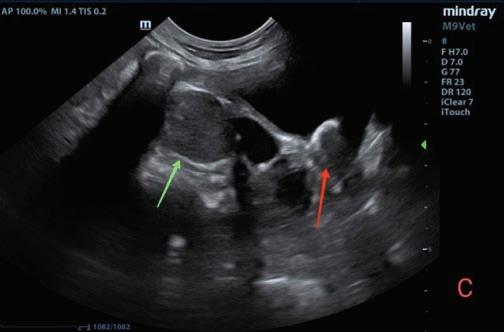

Se realizó una angio-TC de la cavidad torácica para caracterizar la masa mediastínica craneoventral. El estudio se realizó bajo anestesia general y con la paciente en decúbito esternal. Se realizaron series precontraste y post-contraste, inmediatamente y a los 3 minutos tras la administración de un contraste iodado hidrosoluble no iónico (iopromida 300 mg I/ml a una dosis de 600 mg I/kg intravenoso, administrado de forma manual) con cortes de 3 mm de grosor e intervalo 1,5 mm con algoritmo estándar (tejido blando) y pulmón. El estudio de TC se evaluó en ventana de tejido blando, hueso y pulmón, visualizándose en el área craneal al atrio derecho una estructura redon-

deada y bien definida (22UH) de medidas aproximadas 1,95 cm DV x 1,87 CrCd x 2,5 cm LL (Figs. 4 y 5). Tras la administración de contraste, esta estructura se llenó rápidamente de contraste de forma homogénea,

Figura 4. Imágenes de Tomografía Computarizada. Reconstruidas en plano sagital, simples (A) e inmediatamente tras la administración del contraste (B), en plano transversal, simples (C).

observándose una comunicación con el atrio derecho, midiendo el área de la comunicación 1,43 cm. El diagnóstico presuntivo fue de un aneurisma de la aurícula derecha.